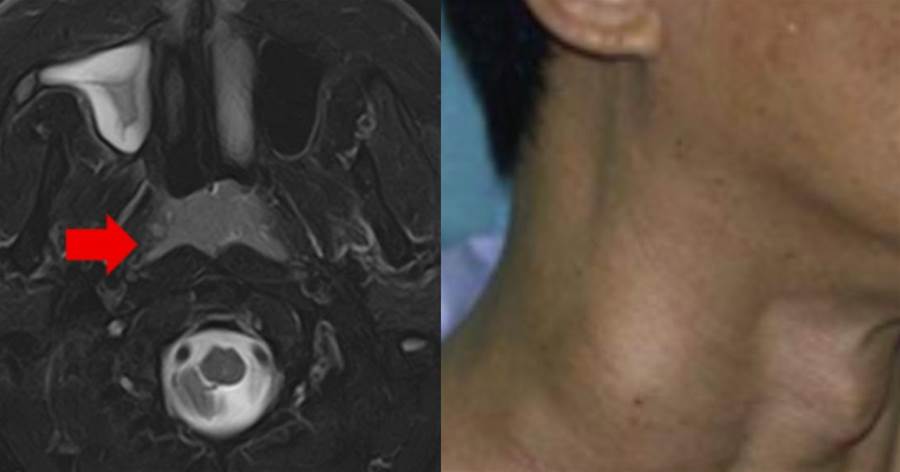

20-30℃水溫下,餐具浸泡1小時細菌量暴增400倍。附著在碗邊的淀粉殘渣,4小時后會培養出超2.8萬/cm²的幽門螺桿菌——這種能在胃酸存活的Ⅰ類致癌物,正是胃癌的隱形推手。

有研究顯示,碗要是泡上10個小時,細菌能暴增7萬倍!特別是那些有油有食物的碗,泡超過4小時,就可能長出黃曲霉素、幽門螺桿菌這些壞東西。黃曲霉素還是世界衛生組織說的一級致癌物,得用超過280°C的高溫才能搞定,長期吃進去,那可真是麻煩大了。以前就是這樣,早上吃完的碗,等著中午一起洗,以后可不能這樣。吃完飯還是趕緊把碗洗了,別讓它們在水里泡太久。